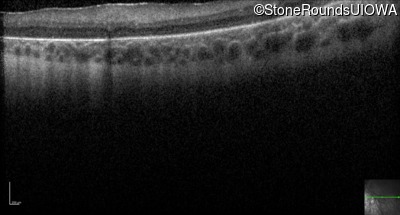

Optical Coherence Tomography - Right -

No Light Perception

Optical Coherence Tomography - Left -

Light Perception